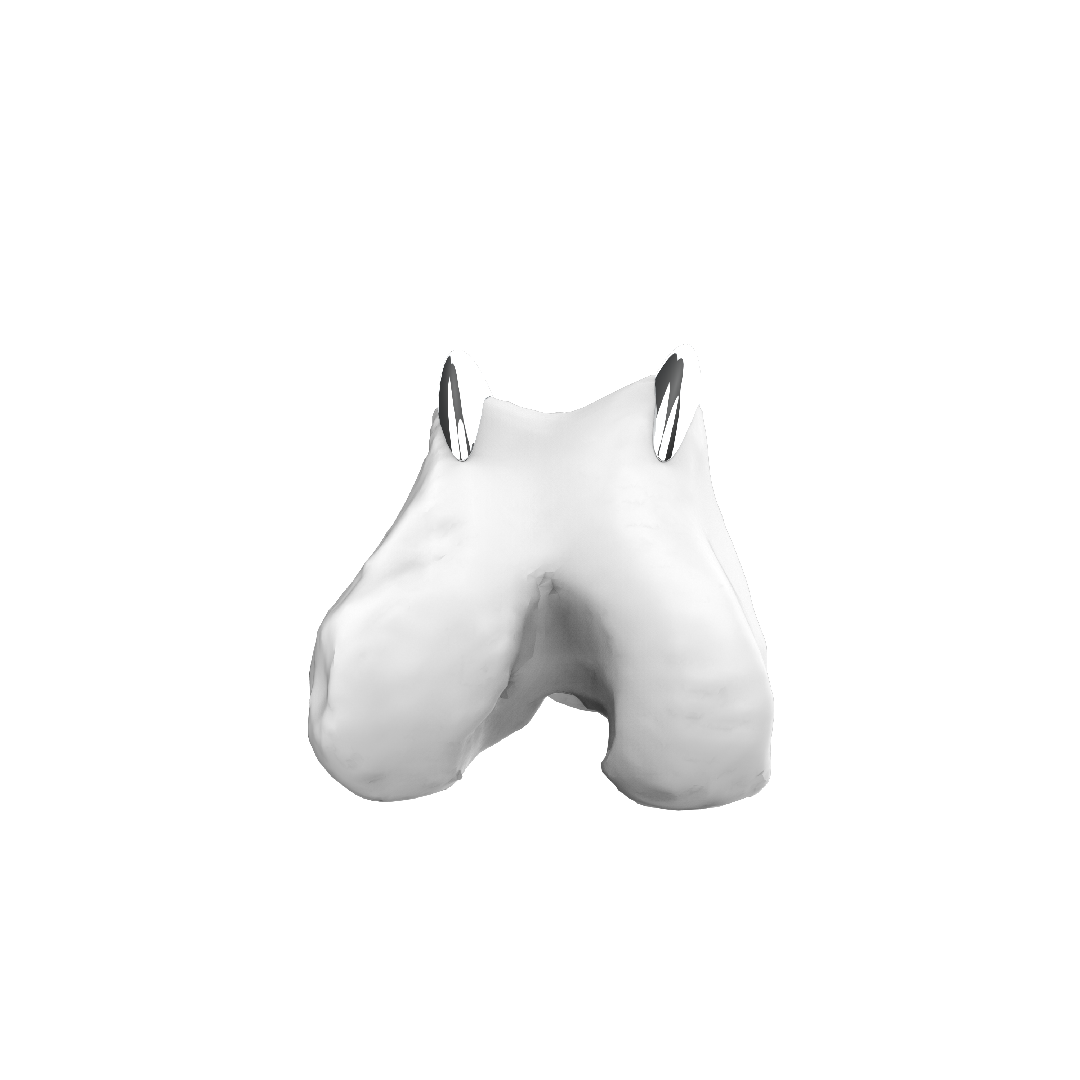

Trochlear Ridge Prostheses (TRP)

TRP è stata progettata per offrire ai chirurghi veterinari un ulteriore strumento nel trattamento della lussazione della rotula.

TRP è un impianto protesico personalizzato che permette di rialzare, secondo necessità, i bordi trocleari del femore, migliorando così il contenimento della rotula nella sua sede anatomica non alterando l’anatomia del paziente.

TRP rappresenta un’alternativa all’intervento di solcoplastica, con l’obiettivo di ridurre al minimo l’invasività della procedura per il paziente e di ridurre i tempi chirurgici.

La personalizzazione della protesi, disegnata sulla base della ricostruzione tridimensionale dell’osso del paziente, consente all’impianto di adattarsi all’osso e non viceversa. La sua applicazione non prevede le ostectomie necessarie nella pratica chirurgica con impianti standardizzati.